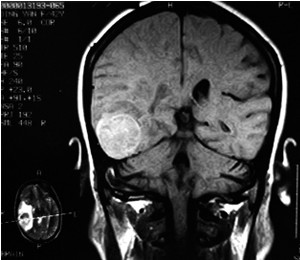

蛛網(wǎng)膜囊腫診斷方法?

蛛網(wǎng)膜囊腫臨床表現(xiàn)與顱內(nèi)占位病變相似。部分患者可有輕癱或癲癇發(fā)作。還可有局部癥狀,如眼球突出和頭部不稱(chēng)等。那么蛛網(wǎng)膜囊腫診斷方法有哪些呢?下面一起詳細(xì)了解一下吧。

蛛網(wǎng)膜囊腫除依據(jù)臨床表現(xiàn)外,可進(jìn)行以下檢查:

3、CT掃描:示局部有低密度區(qū)(CT值近似腦脊液密度),邊界清楚。注造影劑后無(wú)囊壁增強(qiáng)。本癥應(yīng)與腦穿通畸形及顱內(nèi)上皮樣或皮樣瘤鑒別。前者為腦組織缺失,腦脊液充填空腔,故腔與腦室或蛛網(wǎng)膜下腔自由交通,CT掃描可以鑒別。顱內(nèi)上皮樣或皮樣瘤在CT掃描時(shí)與本癥相同均示低密度區(qū),但其邊緣較模糊,外側(cè)壁與顱骨內(nèi)板間常有一段距離,且形狀不規(guī)則。其他尚應(yīng)與慢性硬膜下血腫或水瘤鑒別。